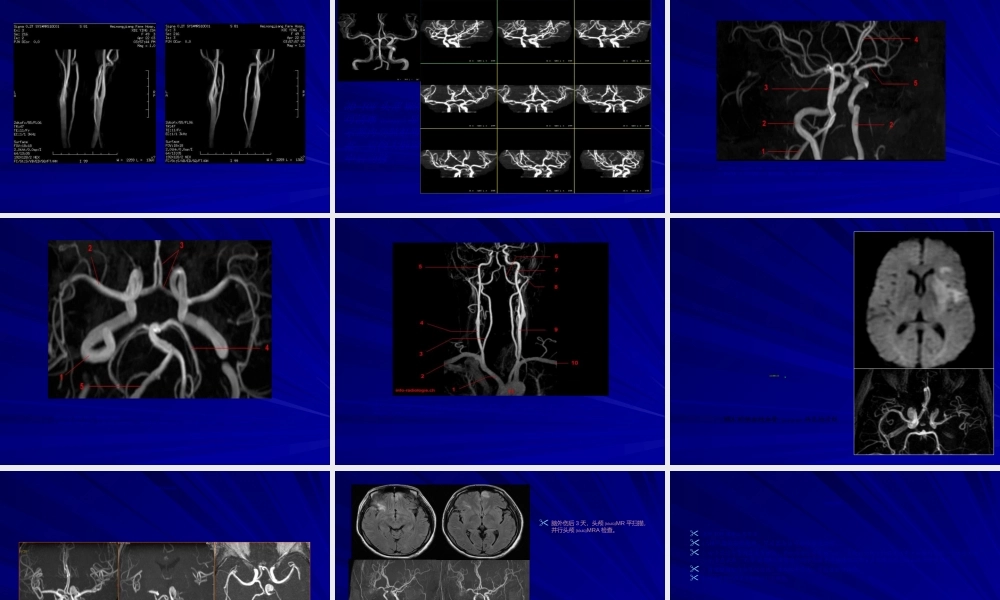

磁共振血管(xuèguǎn)成像(MRA)磁共振血管(xuèguǎn)成像(MRA)MR血管成像(MRangiographyMRA)是利用MR成像技术来描绘解剖组织中血管路径的方法。一般分为:时间(shíjiān)飞跃法(timeofflyTOF);相位对比(phasecontrastPC);对比增强MRA(CE-MRA)。磁共振血管(xuèguǎn)成像(MRA)时间飞跃法(timeofflyTOF)及相位对比(PCMRA)属于不需使用造影剂进行相关成像的技术(jìshù)。磁共振血管成像,是指利用血液流动的磁共振成像特点,对血管和血流信号特征显示的一种无创造影技术(jìshù),是基于GE(梯度回波)序列。对比增强MRA(CE-MRA)是利用顺磁性物质缩短血液T1的磁共振血管成像技术,属于造影剂增强MRA。临床应用最多的是TOF技术及CE-MRA技术,结合我科实际,也是我科重点推广的检查技术。PC是GRE序列,利用血流速度不同(bùtónɡ)引起的相位改变来区分流动和静止的质子。1、PhaseContrast•PC利用双极梯度(tīdù)采集图像+++++000000正相双极梯度-----000000负相双极梯度PC在重建血管(xuèguǎn)时用两次采集相减•静止质子被减去而流动质子保留MRA成像原理磁共振血管(xuèguǎn)成像(MRA)2.TOFMRATOF成像技术是基于血管的流入增强(zēngqiáng)效应,是指静止组织使用梯度回波序列经过连续多次的激励后静止组织处于稳定饱和状态,信号很低或不产生信号;而流入成像层面的血液则由于流入性增强效应而表现出很亮的信号。由于脉冲间隔时间很短,静止组织反复被激发,纵向磁矩不能充分弛豫而处于饱和状态,信号很弱,呈灰黑色;血管内血液流动,采集MR信号时,如果血流速度足够快,成像容积内激发的饱和质子流出扫描层面外,而成像容积外完全磁化的自旋又称不饱和自旋流入扫描层面,纵向磁矩大,发出强信号呈白色,于是血管内外信号差别很大,使血管显影。临床可以进行二维及三维技术进行采集,即:2D-TOF及3D-TOF。TOF是利用GRE序列的流动补偿,依靠流入增强效应区分静止(jìngzhǐ)和流动的质子。Time-of-Flight(TOF)静止质子无位移(wèiyí)而被饱和,产生较少信号流动(liúdòng)质子运动而不被饱和,产生亮信号MRA成像原理TOF成像原理(yuánlǐ)—饱和带饱和(bǎohé)脉冲置于成像容积的流入方向上进入成像容积(róngjī)前的预饱和使血流在进入成像容积(róngjī)后发生饱和,不产生信号层面的编辑必须与血流的方向相对并尽可能垂直于血流的方向,减少层间饱和血管通过层面后质子不被饱和...